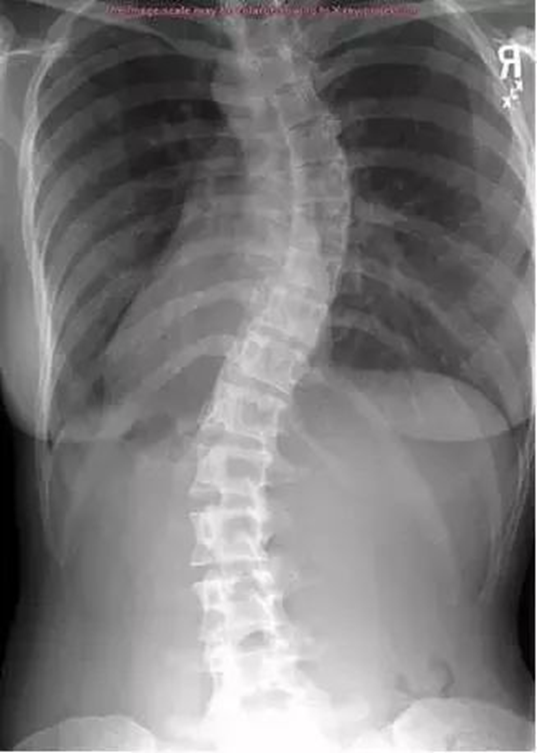

正常人的脊柱从后面看应该是一条直线,并且躯干两侧对称。如果从正面看有双肩不等高或后面看到有后背左右不平,就应怀疑“脊柱侧凸”。这个时候应拍摄站立位的全脊柱X线片,如果正位X线片显示脊柱有大于10度的侧方弯曲,即可诊断为脊柱侧凸。轻度的脊柱侧凸通常没有明显的不适,外观上也看不到明显的躯体畸形。较重的脊柱侧凸则会影响婴幼儿及青少年的生长发育,使身体变形,严重者可以影响心肺功能、甚至累及脊髓,造成瘫痪。轻度的脊柱侧凸可以观察,严重者需要手术治疗。

当初步怀疑有脊柱侧弯时, X线脊柱全长检查是明确诊断的重要检查,此项检查可以明确脊柱具体侧弯角度。进一步出现脊髓压迫症状,怀疑椎体、椎间盘病变时,则需要加做脊柱全长CT或脊柱全长MRI,明确病变情况。